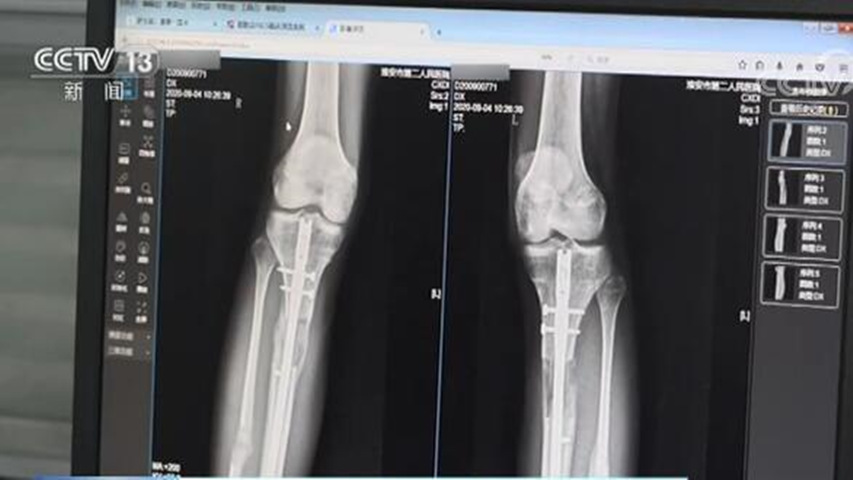

断骨断骨,顾名思义就是把股骨或胫骨切断,然后把可调节的金属钉插进去。

这个既灵活又坚固的玩意儿,可以通过遥控器调节长度。

根据骨骼平均生长速率,医生一般会以每天1mm的长度来调节金属钉。

但这手术的风险也是真的高...

如果医生处理不当,或者病人体质不好,神经损伤、关节挛缩甚至是残疾,都有可能发生。